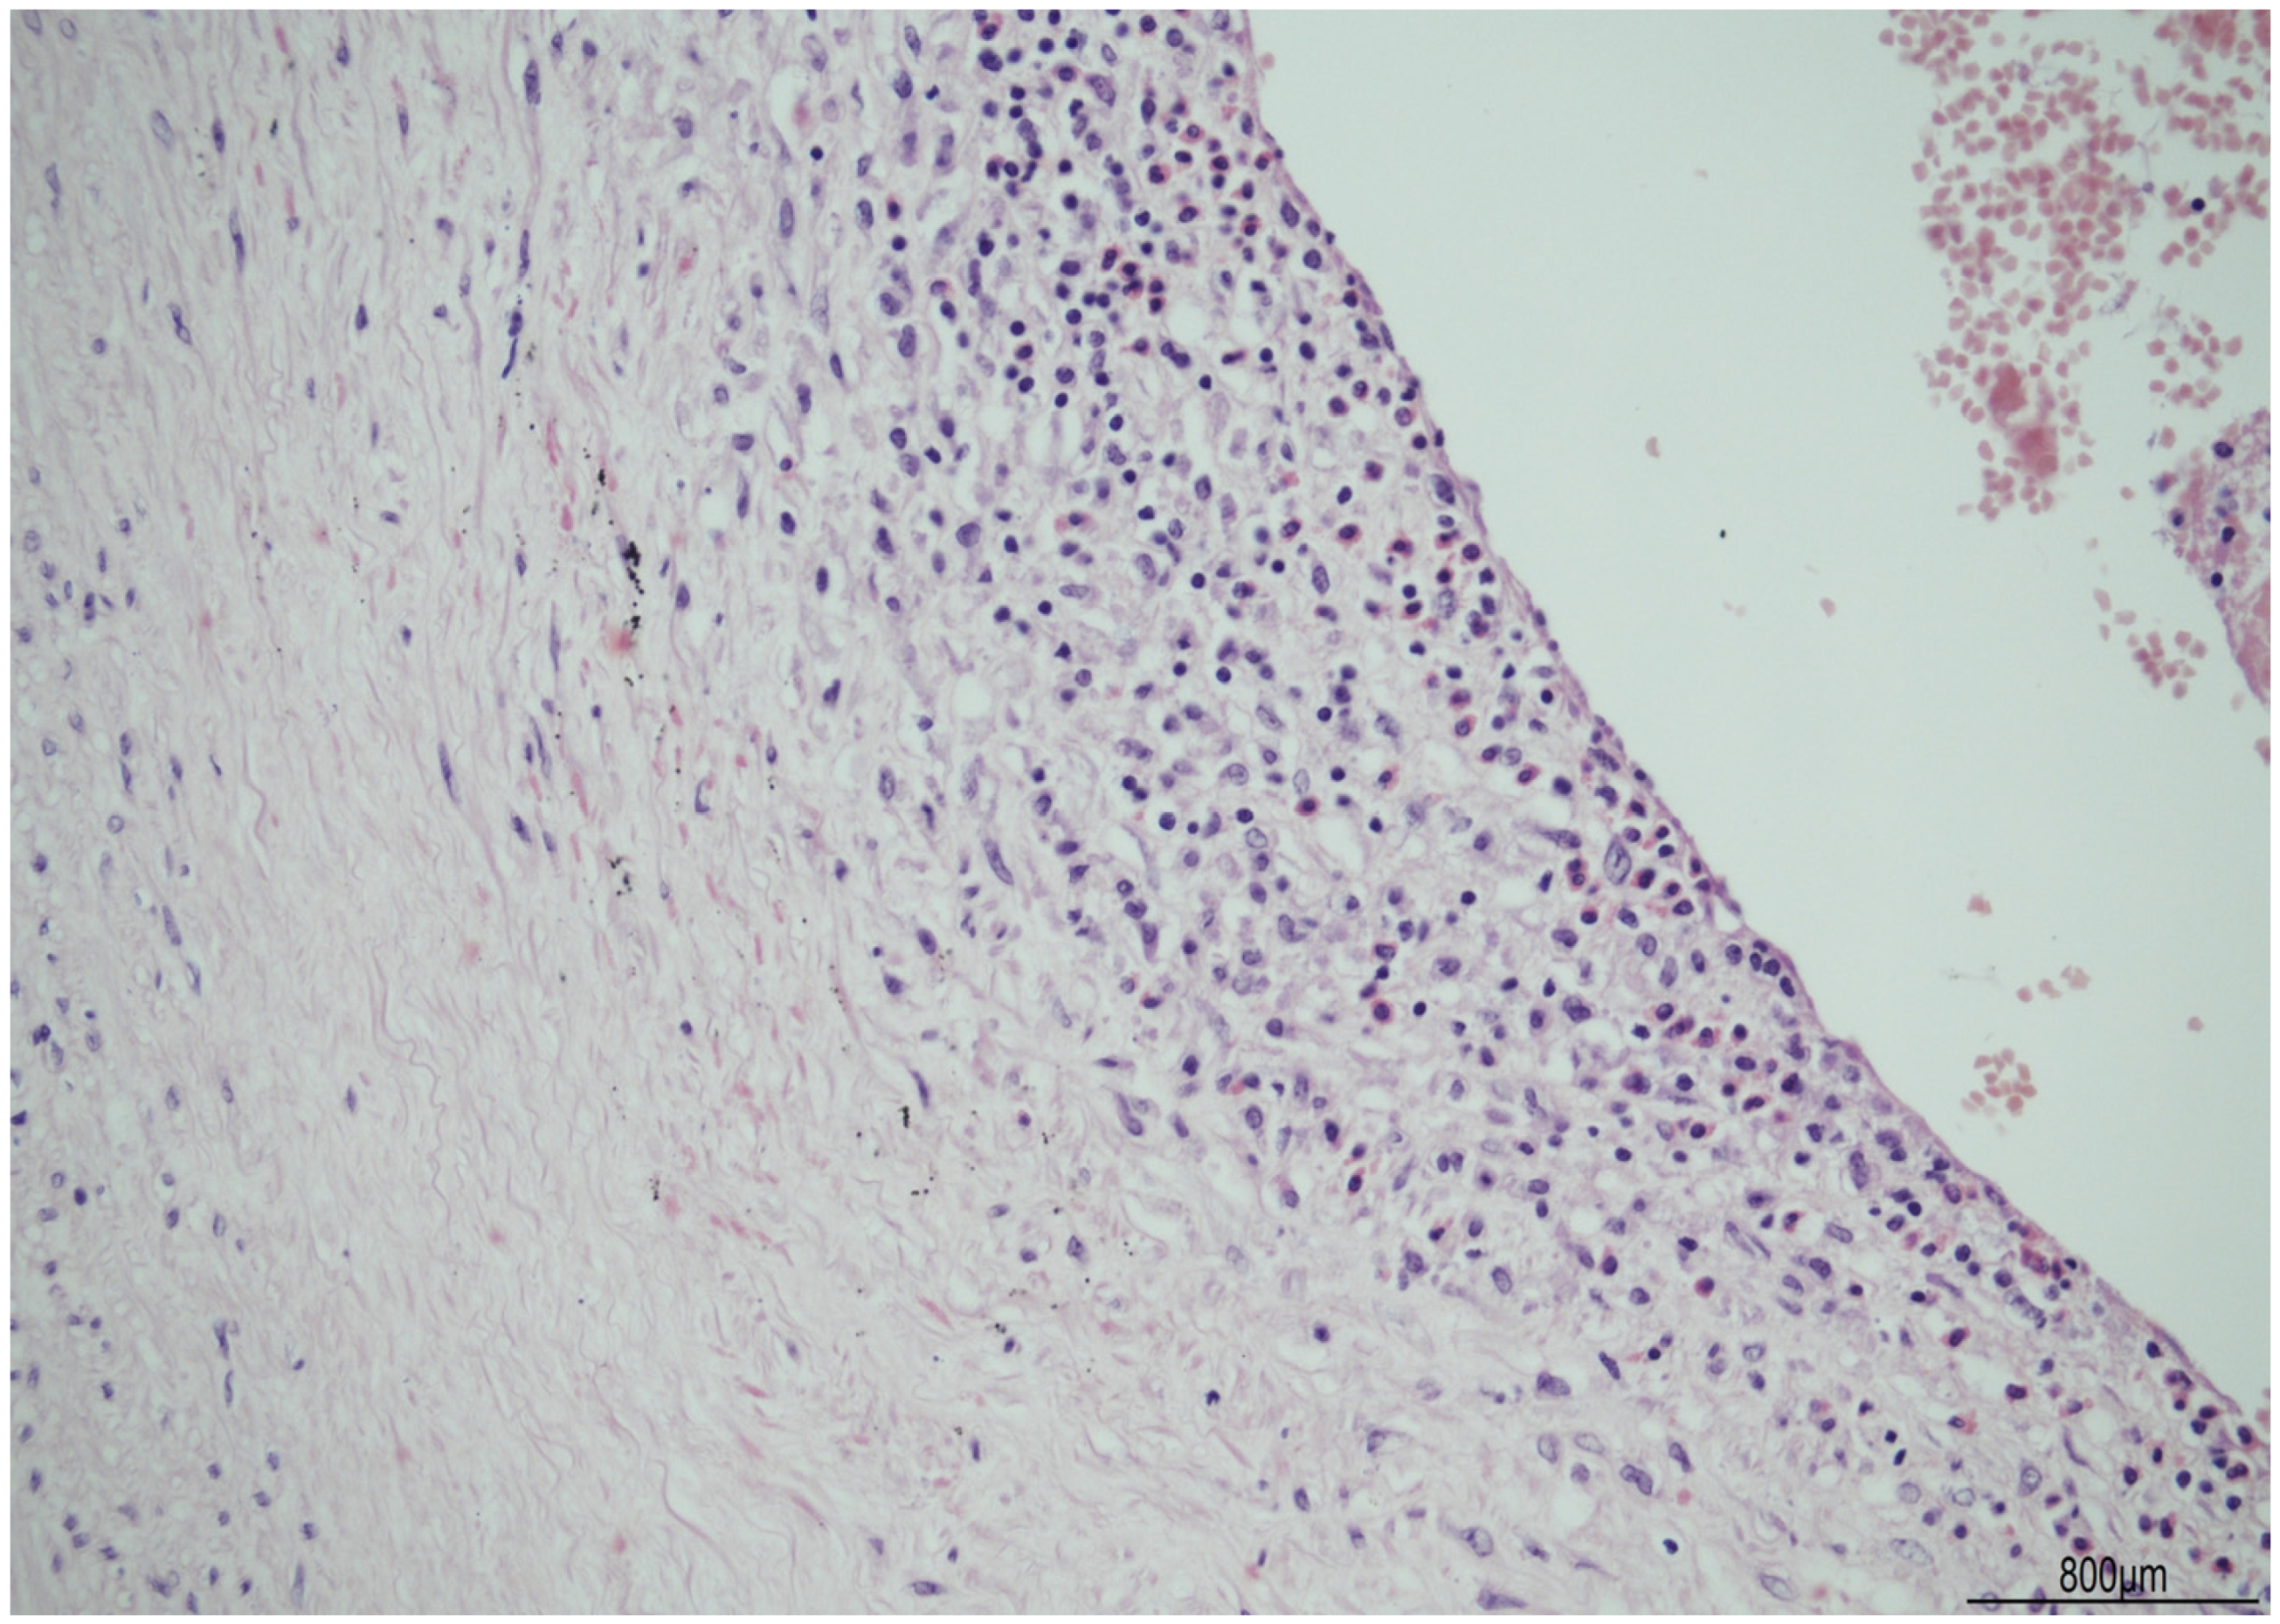

Discordant Eosinophilic/T-Cell Chorionic Vasculitis in a Dichorionic Diamniotic Placenta

2. Case Description